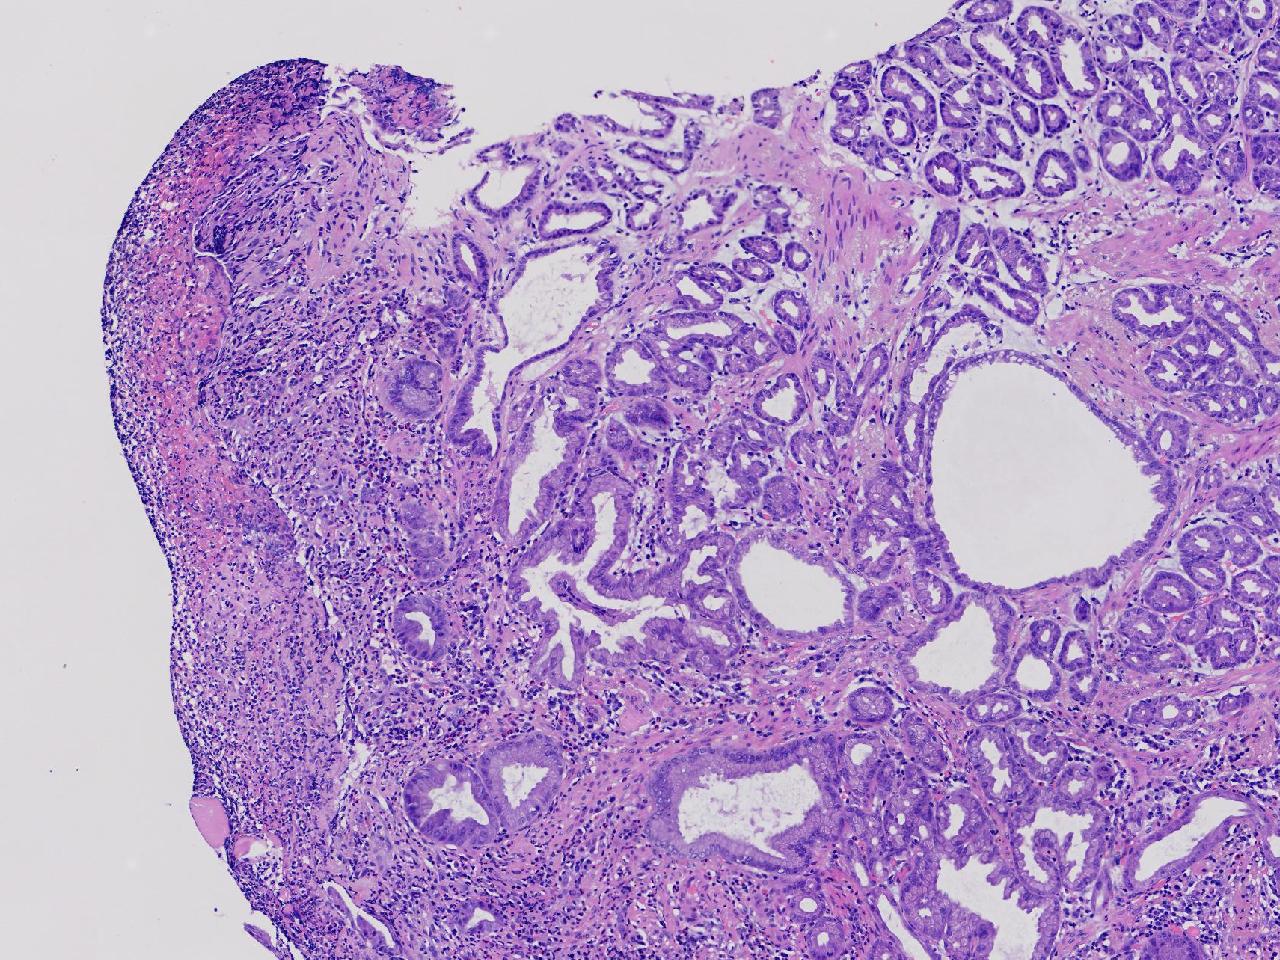

胃体上部见一大小约2厘米的溃疡灶,表覆白苔,周边充血,水肿明显,活检3块。

胃体活检

灰白色不整形软组织3块,直径均0.2厘米。

深在性囊性胃炎,少量溃疡组织

深在性囊性胃炎伴溃疡